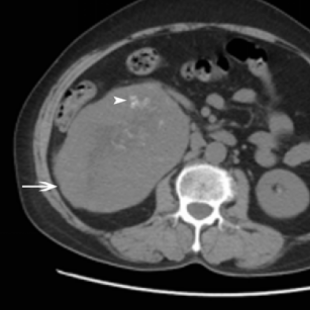

影像学资料:超声和计算机断层扫描显示右肾下极有一个肿块,大小为13.4×15.4×11.4 cm。